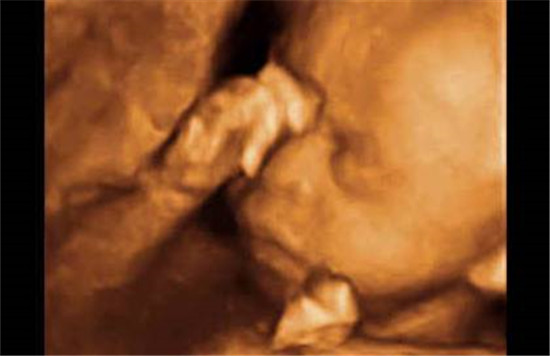

胎儿(相关胎儿专题知识分享)

胎儿专题是妈妈宝宝网胎儿精心为大家收集整理的,提供有关于胎儿的相关知识文章,是妈妈宝宝网以及众多网友分享的有关于胎儿相关经验和体会,以及其有关问题的提问和解答。